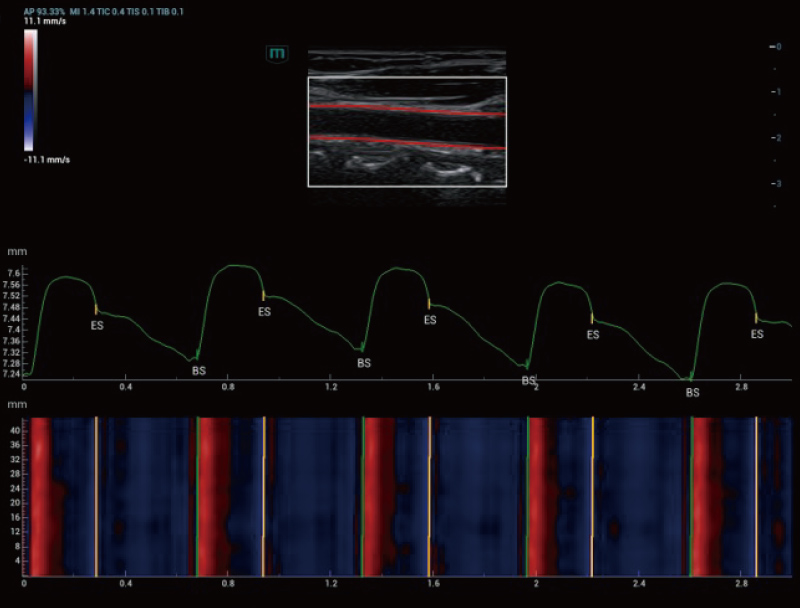

The Resona A20 introduces a new generation of vascular quantitative

analysis tools, featuring RF-data-based vascular pulse wave velocity

and wall shear stress analysis. These advancements aid in the

assessment of arterial vascular sclerosis.

Holo-PWV

V Flow and wall shear stress analysis

Carotid Artery | Holo-PWV